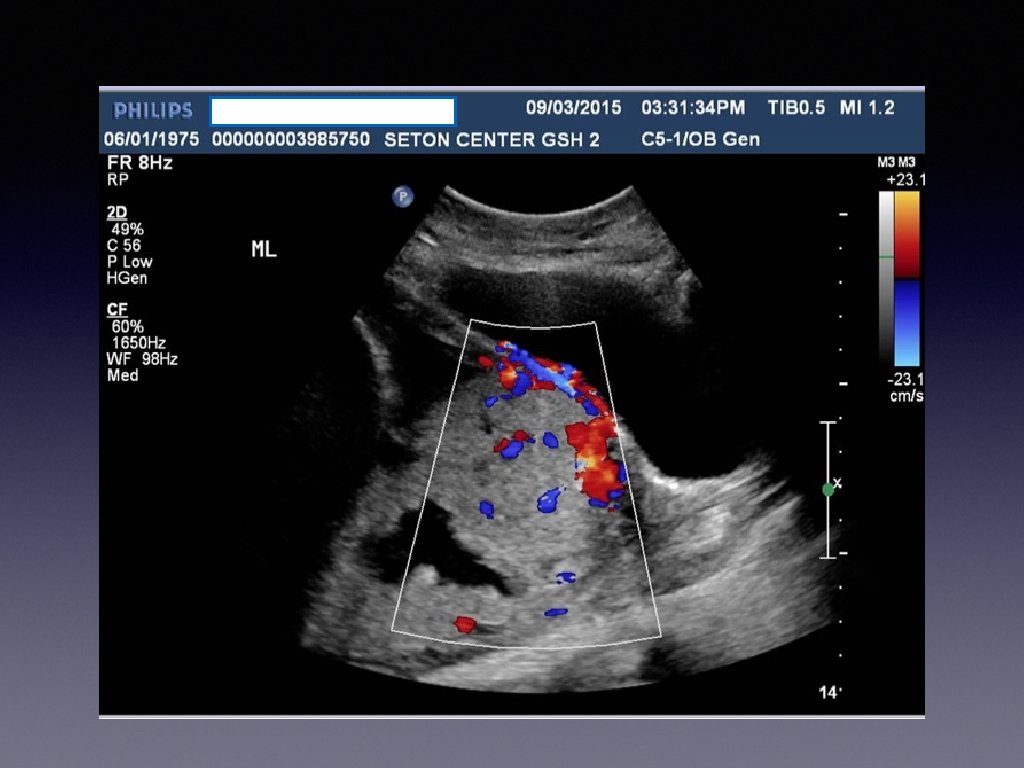

Prenatal Diagnosis • When the diagnosis is made it is usually made by ultrasound in the second or third trimester. • Sonographic findings suggestive are • • loss of normal hypoechoic retroplacental zone • multiple vascular lacunae (irregular vascular spaces) within the placenta “swiss cheese” appearance • blood vessels or placental tissue bridging the uterine-placental margin, myometrialbladder interface, or crossing uterine serosa • retroplacental myometrial thickness < 1 mm • numerous coherent vessels visualized with 3 -D color/power Doppler in a basal view. If sonographic findings are inconclusive or a placenta percreta is suspected, MRI may be useful.

Ultrasound Findings Suggesting Morbidly Adherent Placenta • Third trimester • Loss of normal hypoechoic retroplacental zone • Presence of multiple vascular lacunae within placenta (Swiss-cheese appearance) • Abnormalities of uterine serosa-bladder interface (intertuption of line, thickening of line, irregularity of line, and increased vascularity • Extension of villi into myometrium, series, or bladder • Retro-placental myometrial thickness of< 1 mm • Turbulent blood flow through lacunae on Doppler ultrasonography • Increased subplacental vascularity • Vessels bridging form placenta to uterine margin • Gaps in myometrial blood flow